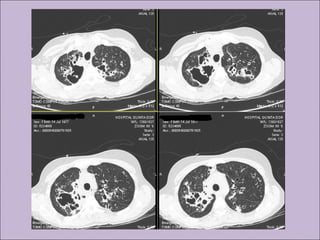

C) Anormalidades persistentes à radiografia de tórax

Bronquiectasias

Atelectasias

Hemoptise

Pneumotórax